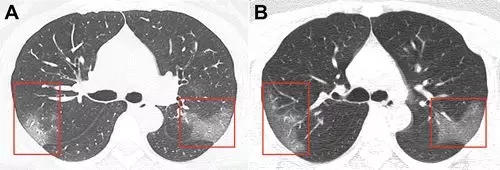

病例2,41岁女性,去了一趟武汉,

回来后,开始发热咳嗽,

4天后,她感觉呼吸困难,

去医院X线胸部拍片,检验血液,

都没有发现有啥异常。

但是CT扫描发现

两侧肺周边出现多处斑片状毛玻璃样显影。